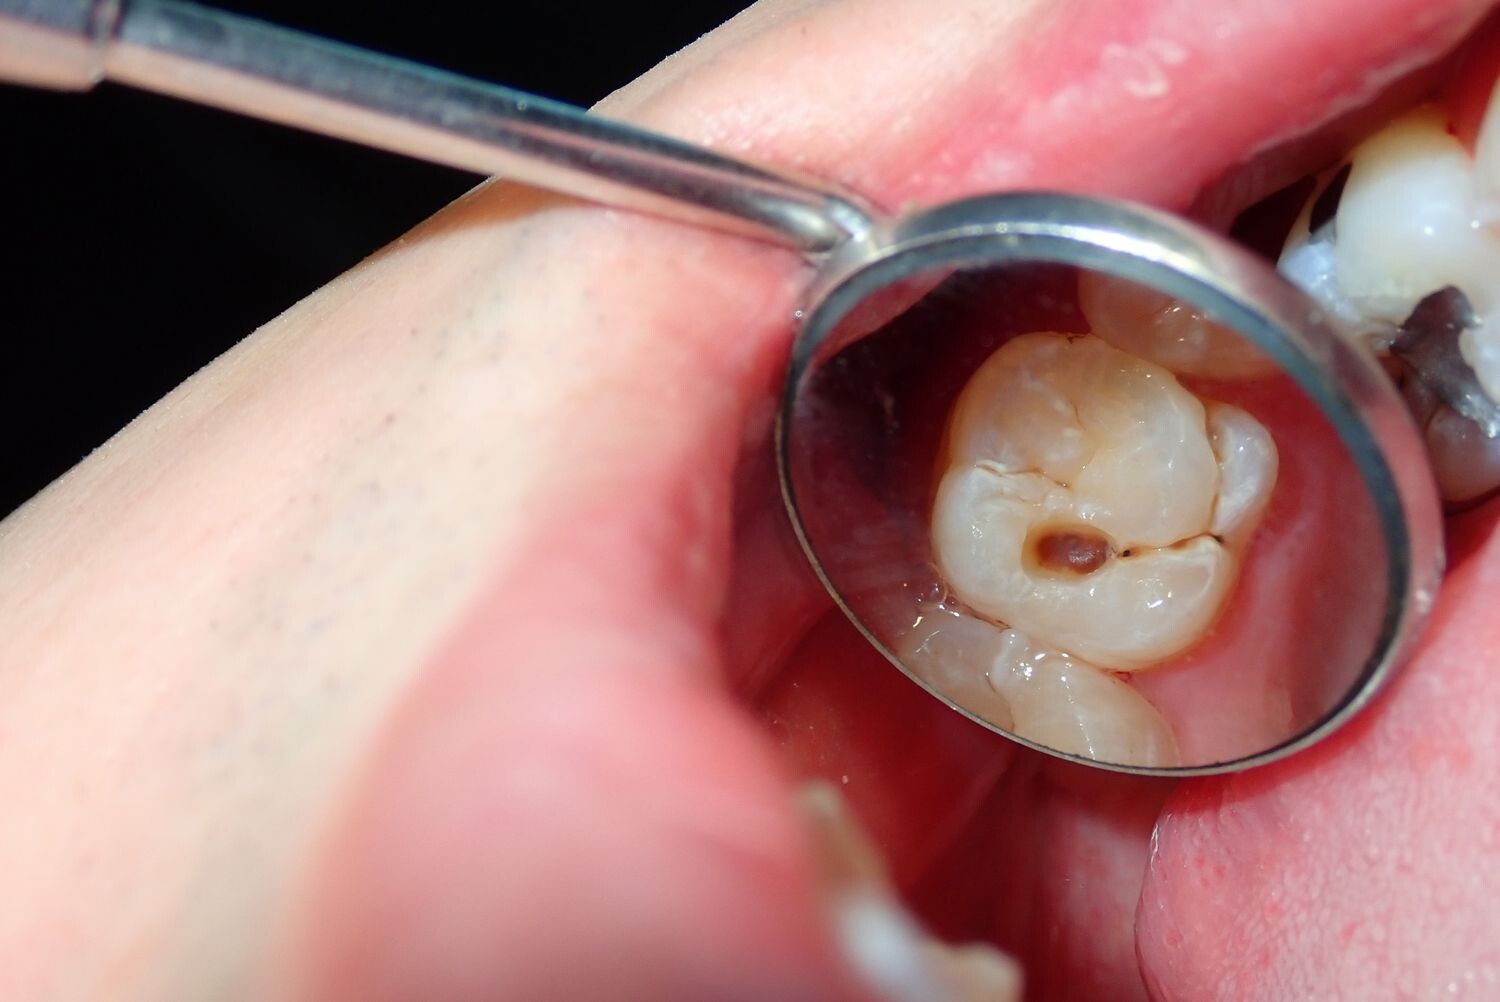

Cavities are pretty common. As the National Institutes of Health points out, the only condition more common than a cavity is the common cold. If you've never experienced tooth decay, you might wonder, "What does a cavity feel like?" The answer depends on the stage of the cavity and what foods you eat. Some foods, such as sweets, might trigger the pain of a cavity more than others.

How Cavities Form

Your mouth is naturally full of germs. Some of those germs are perfectly healthy, but others can be harmful. When you eat something sugary, such as candy or even potato chips, or drink a sugary beverage, the germs feed on the sugars in the substance. This produces acid, which is strong enough to wear away tooth enamel if not cleaned off quickly enough. In the end, a dental cavity begins to form.

In the early stages, a cavity can be reversed, as the National Institute of Dental and Craniofacial Research notes. Brushing your teeth with a toothpaste that contains fluoride can help restore the enamel and reverse the effects of cavities.

Signs of a Cavity

What does a cavity feel like? In the earliest stages, the answer might be nothing. There are no nerves in your tooth enamel, so when the decay is in that layer, you likely won't feel a thing. Once the decay has progressed enough to reach the softer tissues inside the tooth, where the dentin and nerves are, you might notice signs of a cavity. Your teeth might feel sensitive and you could feel some pain, especially after eating sweets, hot foods or cold foods. The pain can be fairly mild or sharp and intense. Some people with cavities also feel pain when biting down.

Depending on the size of the cavity, you may be able to see evidence of it in your mouth. Cavities sometimes create visible holes in the teeth. They can also create stains that are black, brown or white on the surface of the tooth.

Tooth decay

As tooth decay progresses, it can reach the softer inner layers of the tooth, called dentin and pulp, resulting in sensitivity to hot, cold, or sweet foods and drinks and eventually leading to a toothache. If left untreated, tooth decay can result in an abscess, a painful infection at the root of the tooth that can cause severe pain and swelling. Adhering to your routine dental check-ups, practicing good oral hygiene, and eating a healthy diet can help prevent tooth decay and the resulting toothache.